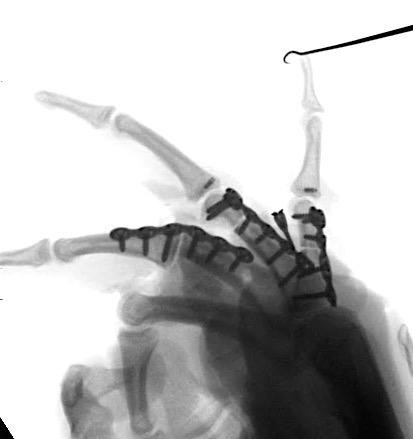

A 20-year-old male suffered a complex multi-digit injury of the right hand requiring revascularization and stabilization of both proximal phalanx and PIP joint fractures (Figs 5 - 8). Multiple plates, including the rotation correction plate from the 1.5 module of the VA Locking Hand System were used for fixation. The Variable Angle Locking system is ideal when only two screws, either proximal or distal, are able to be inserted due to space limitation.

One major advantage of variable angle technology in very distal phalangeal fractures is the ability to be extremely flexible with a wide range of fixation options. Freedom of implant placement assists early mobilization, vital in these complex fractures with associated soft-tissue trauma.